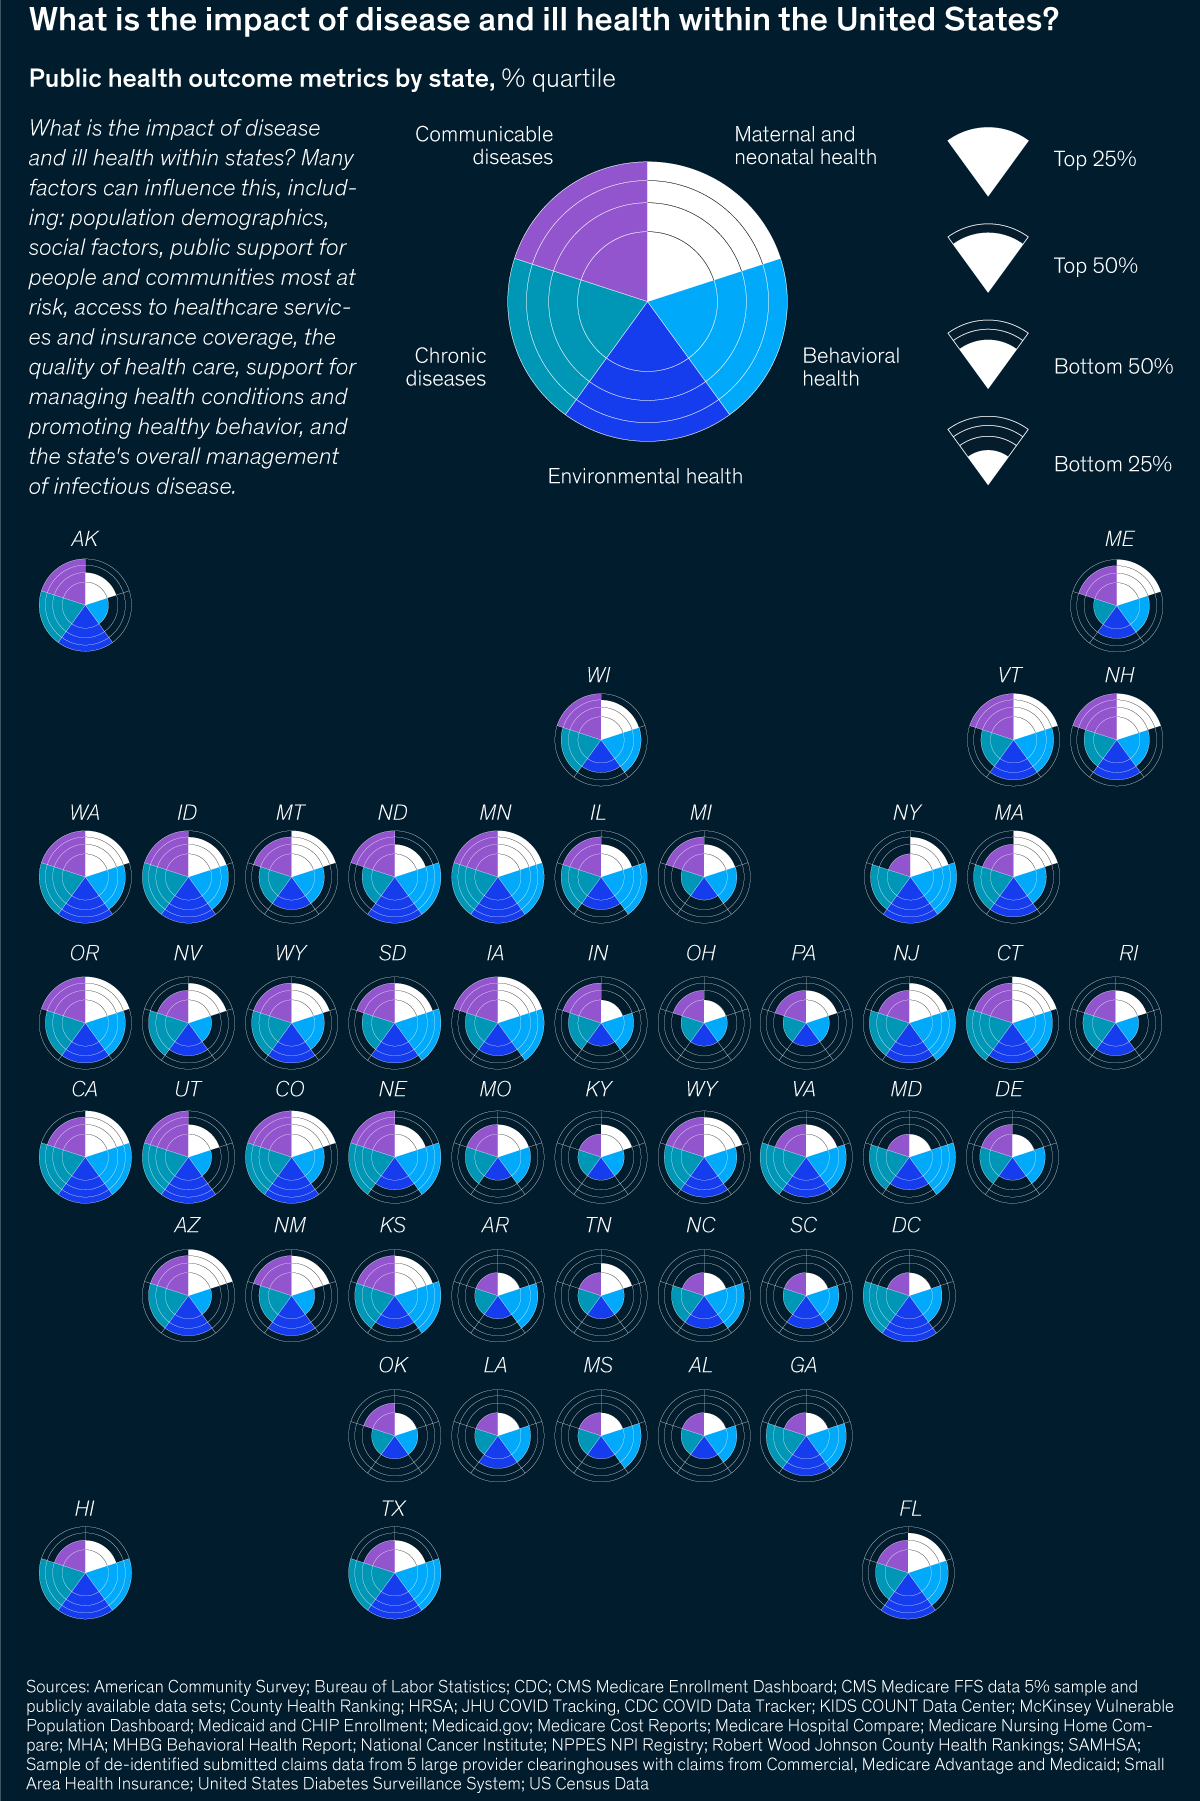

What AI can do for human health

A new edition of The Next Normal Yes, I'm still interested The Next Normal | What AI can do for human health Share these insights